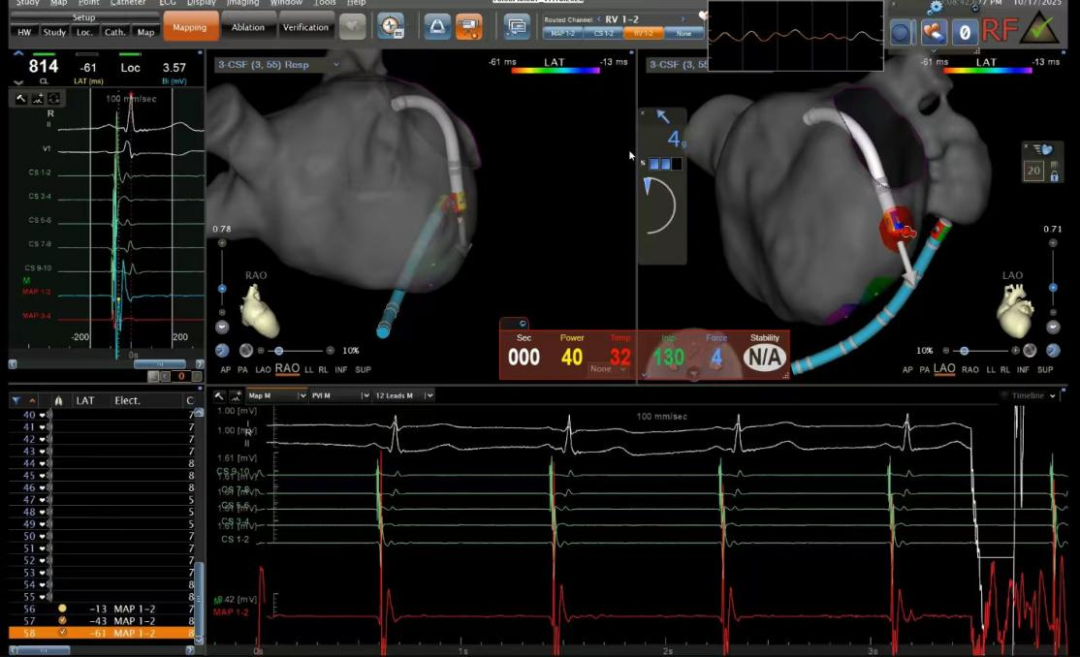

在心血管内科主任廉哲勋、病区主任李健的指导下,路军副主任医师、李姗副主任医师精准操作,配合三维心腔内超声引导进行标测与定位。随着射频能量的精准释放,异常电路被成功阻断,手术顺利完成。手术过程中,患者保持清醒,腹中胎儿一切正常,当听到手术成功的消息时,她流下了喜悦的泪水。

手术团队精确定位、消融靶点

绿色射频消融手术采用的心脏三维电解剖标测系统,如同精密的“心脏GPS”,可在电脑上实时构建出患者心脏的立体模型,医生可通过股静脉将细小的消融导管送入心脏,在三维系统的精准导航下,迅速定位导致心动过速的“异常电路”(旁路或双径路),进行精准的射频消融。